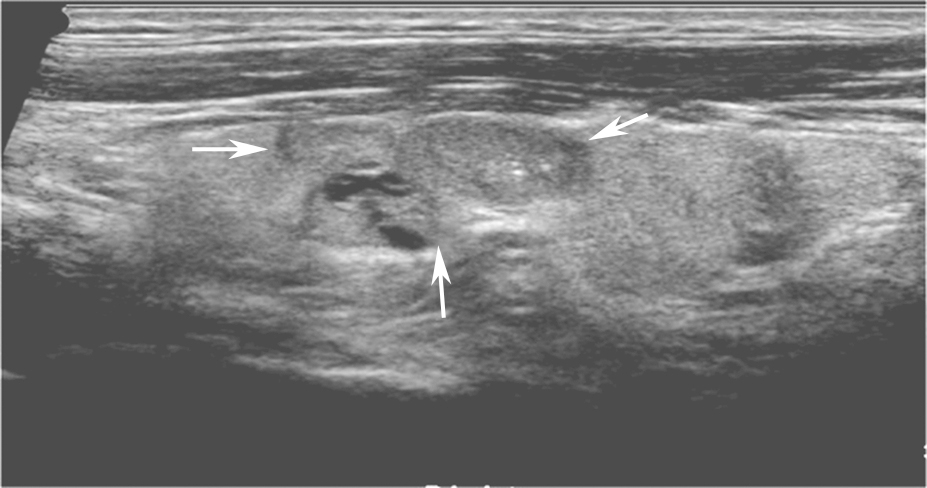

(十)甲状腺滤泡癌

甲状腺滤泡癌和滤泡腺瘤在超声上鉴别有一定困难,即使是FNA细胞学也很难鉴别。但有报道认为:与甲状腺乳头状癌不同,甲状腺滤泡癌常为等回声或高回声,微小钙化很少见,病变多伴有厚薄不一的低回声晕或者局部低回声晕。彩色多普勒血流信号丰富也是该类病变的特点之一(图11、图12)。

:内部回声不均伴厚薄不一低回声晕.jpg)

图11右侧颈部纵切面:甲状腺右叶中部中等回声(箭头所示):内部回声不均伴厚薄不一低回声晕